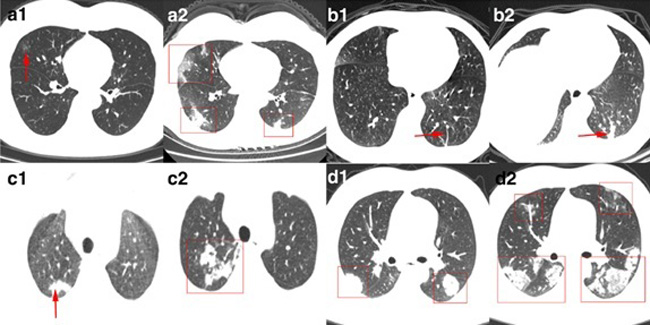

Минздраве и в медсанчасти №4 заверили, что прилагают все усилия, чтобы ускорить работу и ввести прибор в эксплуатацию как можно раньше. ФОТО © MEDRADIOLOGY.MOSCOW Реклама. ООО